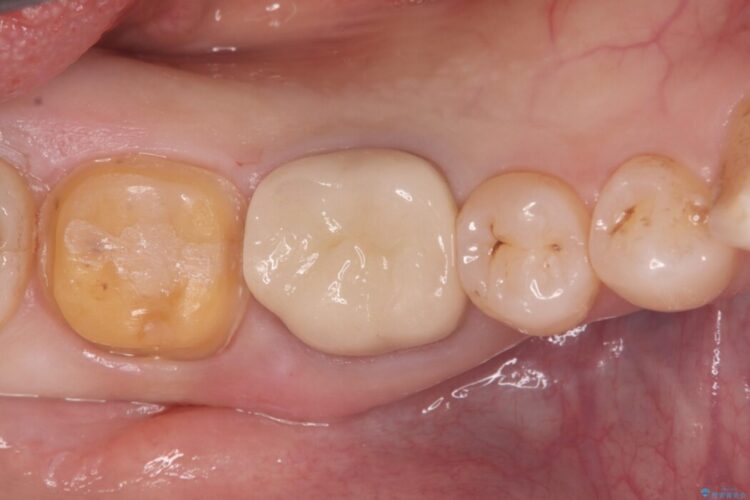

古い銀歯と中の虫歯をしっかりと取り除き、耐久性の高いセラミッククラウンで補強しました。

型取りには精密なシリコン材を使い、細菌の再侵入を防ぎます。

セラミックは見た目が美しいだけでなく、汚れがつきにくく、良好な口腔衛生状態を維持しやすくなり長期的に安心して使用できる状態へと整えることができました。